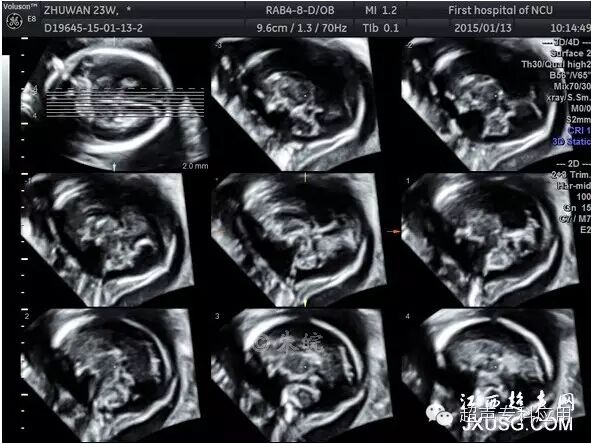

1.3 三维重建颅脑正中矢状平面 由于胎儿在官内的位置,二维超声往往只能获取颅脑横断面。颅脑畸形的超声筛查通过胎头横断面扫查即可完成,但对某些横断面上出现的异常改变或怀疑颅脑中线结构异常,则需要在颅脑矢状平面上进行诊断。胼胝体缺失、Dandy-walker综合征是较为常见的中枢神经系统异常,临床上常常需要明确诊断或进行鉴别诊断,若不进行颅脑矢状平面的扫查,有时会给诊断带来困难。三维重建颅脑正中矢状平面能够显示透明隔、胼胝体、第三脑室、第四脑室及小脑蚓部、后颅窝等中线结构,测量小脑蚓部径线,这是二维超声难以达到的。有文献报道显示,与二维超声相比,利用三维超声诊断颅脑异常的敏感性从二维的82.7%提高到三维的93%。

胎儿正中矢状切面三维容积对比成像

1.4 多平面断层扫查 这种三维超声形式与CT断层扫描相似,连续平行的断面图,就如慢慢平行移动探头,将检查部位从上至下或从左到右显示一遍。每幅断面图之间的距离可以调节,间隔或较宽、或较窄。连续平面可以是横切,可以是纵切,也可以是冠状切。这一技术在胎儿颅脑及心脏的检查中应用较广,如颅脑横切面或冠状切面的连续多平面检查。

胎儿头部三维多平面断层成像(TUI)